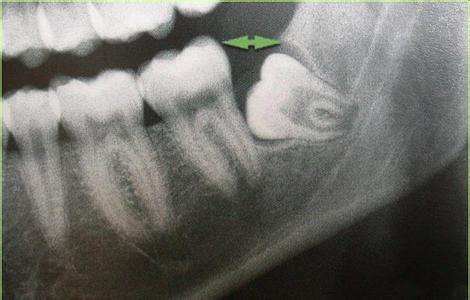

智齿长在肉里要拔掉吗?首先要拍片检查,确定牙齿的生长情况:

1)拍片后确定智齿的位置方向,如果有足够的空间、方向正常,医生评估能顺利长出的话,可以考虑保留等待智齿自然长出(如果有必要可切开牙肉助其长出)

2)如何拍片后牙齿位置不正,无法长出还对旁边邻牙造成威胁的,应当尽早拔除。若智齿没有及时拔除导致邻牙蛀牙的例子很多。(80%的人的智齿位置长的都不正~)

4)长歪的智齿,也就是阻生智齿,也有可能因为位置不正,长不出来,埋伏在牙床里。

在智齿开始萌发时,就先给智齿拍个片,就能很清楚的看到智齿的情况了。